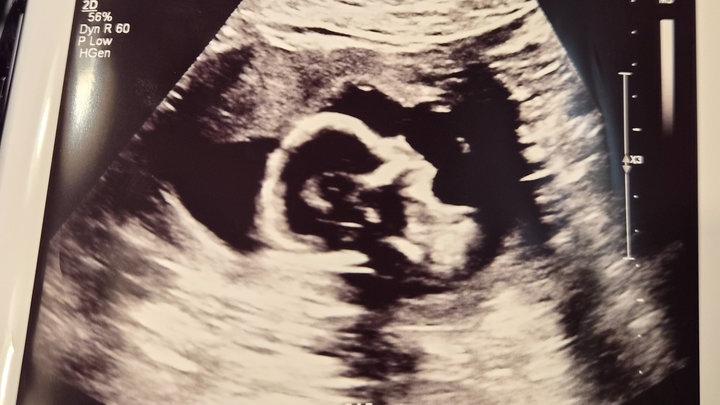

For those who may not know, Zach and I are expecting our third baby — our second little girl. During this pregnancy, we’ve faced several concerns that ultimately led to a diagnosis of placenta previa and placenta accreta. While previa is relatively common, accreta is rare and can be life-threatening for both mom and baby.

For the safety of both me and our baby, we have made the unexpected and very difficult decision to move back to California so I can be treated at UC Davis, where there are specialists experienced in managing placenta accreta. Baby girl will be delivered early, likely around 34–35 weeks. It is also very likely that I will undergo a hysterectomy at the time of delivery to prevent and control severe blood loss. We are preparing for a possible NICU stay for her, as well as ICU time and several days of hospitalization for me.